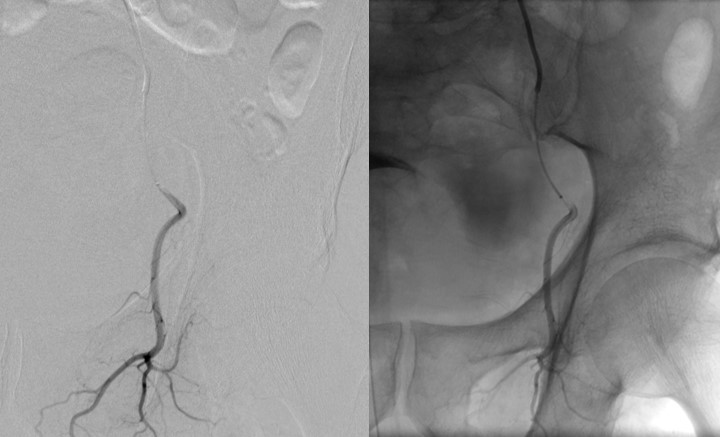

lateral sacral artery

The iliolumbar travels in a cephalad direction which is an identifying feature. It may arise directly off of the internal iliac, rather than a posterior trunk. The lateral sacral artery travels medially and posteriorly in its relationship with the sacrum. There may be more than one lateral sacral branch.

obturator artery

Helpful is the characteristic inverted ‘Y’ at the obturator foramen. This can be a site of bleeding with pelvic trauma. An interesting and important variant is worth mentioning here. The obturator artery can also arise from, or anastomose with, the inferior epigastric artery, running along the posterior aspect of the superior pubic ramus. It can be an unwelcome surprise to a surgeon and can be difficult to control, earning the moniker ‘corona mortise’ or crown of death.